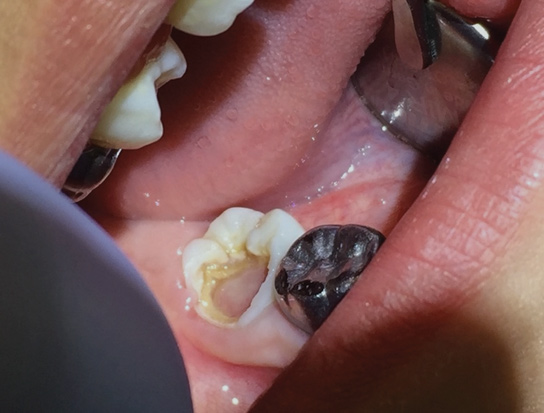

These findings demonstrate that the pulpal diagnostic term asymptomatic irreversible pulpitis needs to be updated. This diagnosis represents a tooth that presents with clinical and radiographic evidence of caries (Figure 2) and responds normally to clinical sensibility testing to cold. The AAE Consensus Conference Recommended Diagnostic Terminology defines asymptomatic irreversible pulpitis as "a clinical diagnosis based on subjective and objective findings indicating that the vital inflamed pulp is incapable of healing. Additional descriptors: no clinical symptoms but inflammation produced by caries, caries excavation, trauma."12 In reality, this diagnosis can technically only be confirmed histologically. But, according to the results of the study conducted by Ricucci and colleagues13, teeth that responded normally to cold testing demonstrated only a mild to moderate accumulation of chronic inflammatory cells beneath the tubules that were affected by caries, and the inflammation did not extend through the entire portion of the pulpal tissue. Therefore, the pulp of a carious tooth that responds normally to cold testing should be diagnosed as normal pulp, not asymptomatic irreversible pulpitis. A more pertinent use of the diagnostic term asymptomatic irreversible pulpitis would be for cases involving a pulp polyp or internal resorption of a vital tooth (Figure 3).

(2.) Bitewing radiograph of tooth No. 18 with radiographic evidence of distal carious defect. This tooth tested within normal limits to cold sensibility tests. Under the current diagnostic terms, the pretreatment pulpal diagnosis would be asymptomatic irreversible pulpitis.

Figure 2